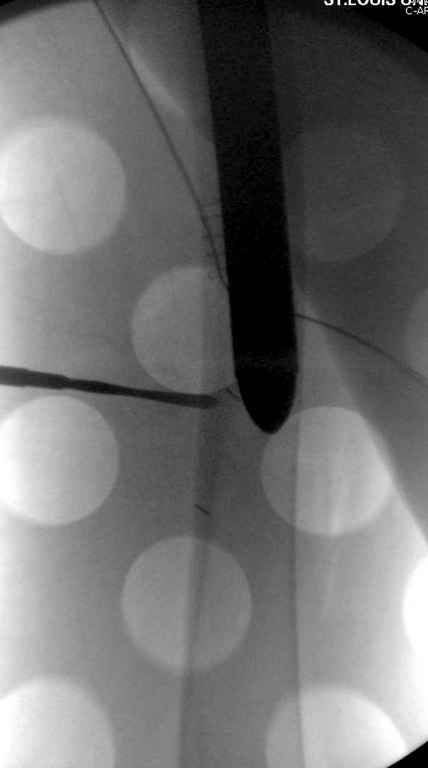

В приложении похожий пример, к счастью, пациентка появилась не после, а "за полчаса" до протрузии. Пересинтезировали с исправлением ошибок.